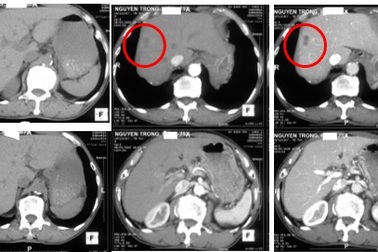

Đau thắt lưng đi khám, bất ngờ phát hiện khối u trong ganPhát hiện u ở gan phải, cụ ông (75 tuổi), Hà Nội đi khám chuyên khoa ung bướu vì tưởng mắc ung thư gan. Tuy nhiên, kết quả sinh thiết lại khẳng định ông bị u gan do ký sinh trùng.

Khoảng 1/3 bệnh nhân phát hiện ung thư gan trong lần khám đầu tiênPGS. TS Trịnh Thị Ngọc cho biết: “Theo kết quả thống kê của Chuyên khoa Gan Mật - Bệnh viện Đa khoa MEDLATEC, trong 100 bệnh nhân lần đầu tiên đi khám chuyên khoa Gan Mật, có từ 30 - 40 bệnh nhân bị các bệnh lý về gan mật ở mức độ nguy hiểm, thậm chí ung thư gan giai đoạn cuối.